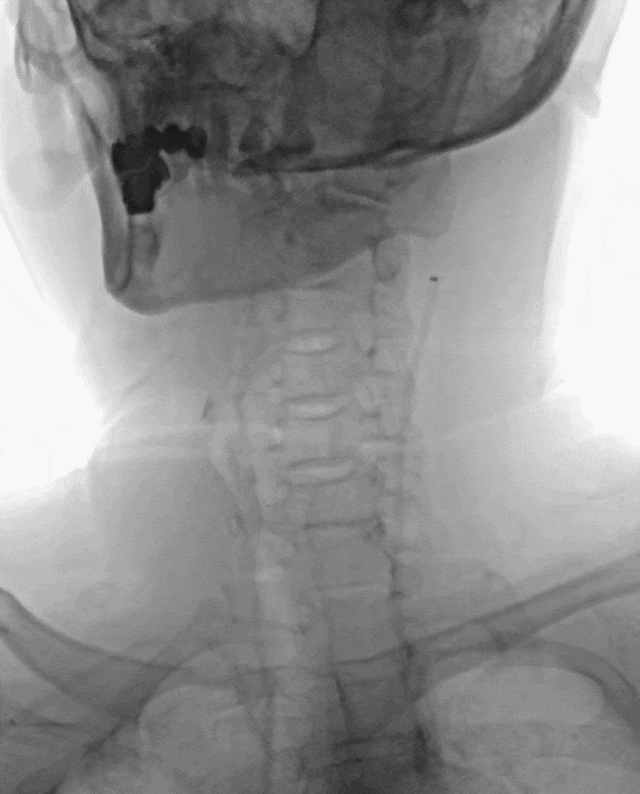

5F 125cm Sim2造影导管携5.5F Introsky X导管鞘成袢后超选左侧ICA。

什么叫桡鞘【例久弥新】寻道于桡——瑞康通5.5F Introsky X导管鞘经桡取栓一例_https://www.jmylbn.com_新闻资讯_第13张

什么叫桡鞘【例久弥新】寻道于桡——瑞康通5.5F Introsky X导管鞘经桡取栓一例_https://www.jmylbn.com_新闻资讯_第14张

泥鳅导丝、SIM2造影导管、5.5F Introsky X导管鞘同轴下继续跟进,尽可能高到位,随后引入V-18导丝。